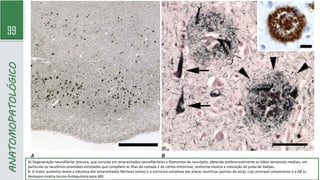

ANATOMOPATOLÓGICO

A) Degeneração neurofibrilar precoce, que consiste em emaranhados neurofibrilares e filamentos de neurópilo, afetando preferencialmente os lobos temporais mediais, em

particular os neurônios piramidais estrelados que compõem as ilhas da camada 2 do córtex entorrinal, conforme mostra a coloração de prata de Gallyas.

B. O maior aumento revela a natureza dos emaranhados fibrilares (setas) e a estrutura complexa das placas neuríticas (pontas de seta), cujo principal componente é a Aβ (o

destaque mostra imuno-histoquímica para Aβ).